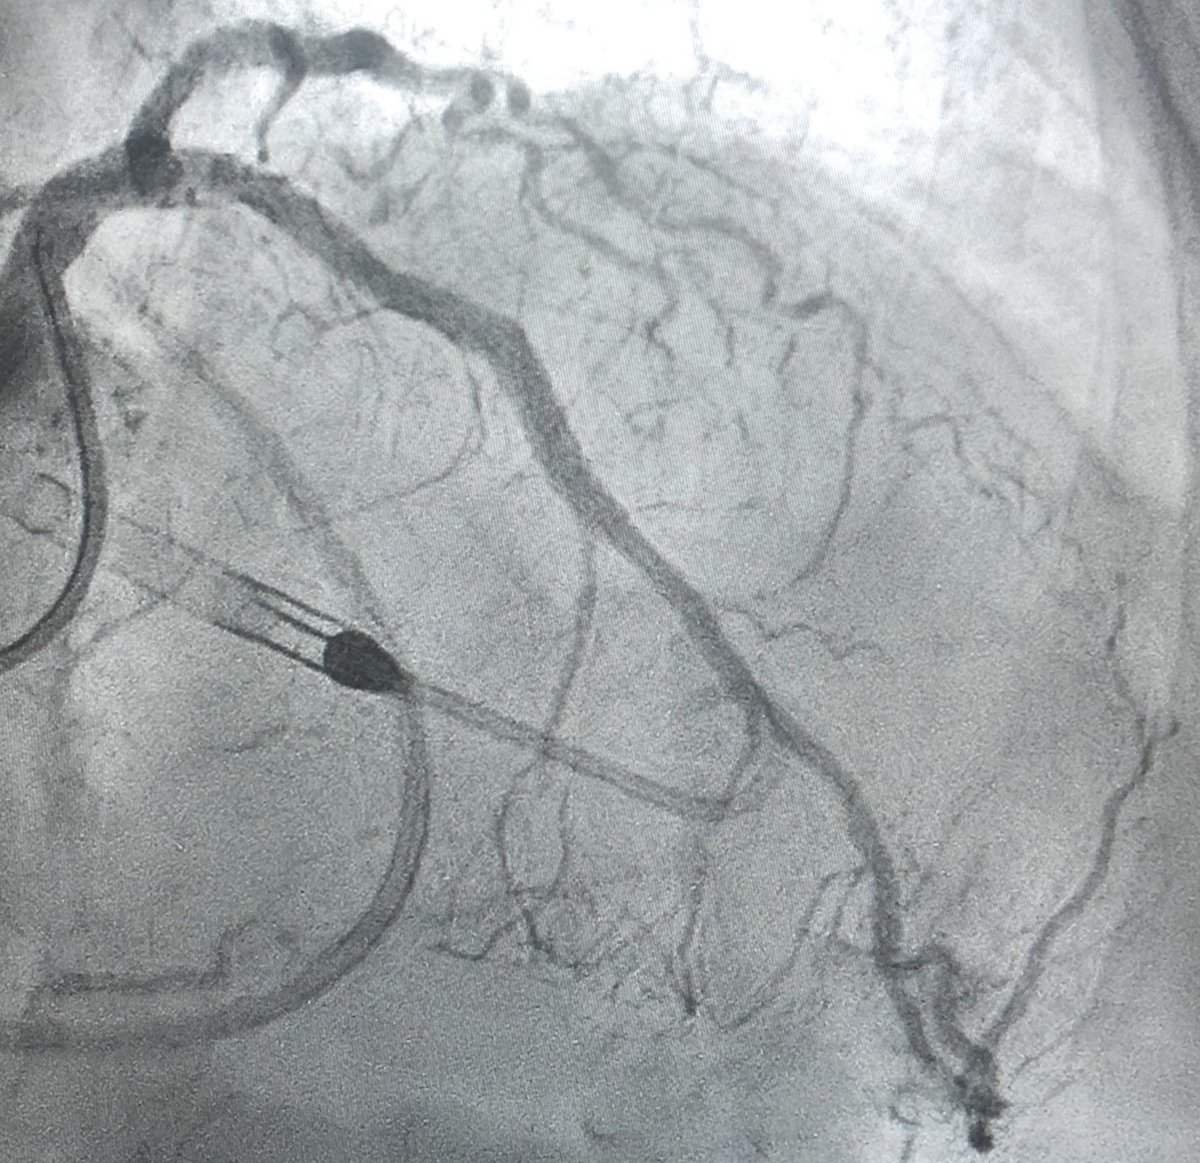

62 y/o male presents with NSTEMI. Boarded for cath in am. Prior to cath VT arrest and on vasopressors Findings at cath, severe LAD, CTO LCx, CTO RCA. LVEDP 34mmhg, EF 10%. Severe PAD. Rx with IC fellow sticks #PercAx Impella and IVUS guided revasc. Now off vasopressors.

DrAmirKaki's tweet image. 62 y/o male presents with NSTEMI.  Boarded for cath in am.  Prior to cath VT arrest and on vasopressors Findings at cath, severe LAD, CTO LCx, CTO RCA.  LVEDP 34mmhg, EF 10%.  Severe PAD.  Rx with IC fellow sticks #PercAx Impella and IVUS guided revasc.  Now off vasopressors.